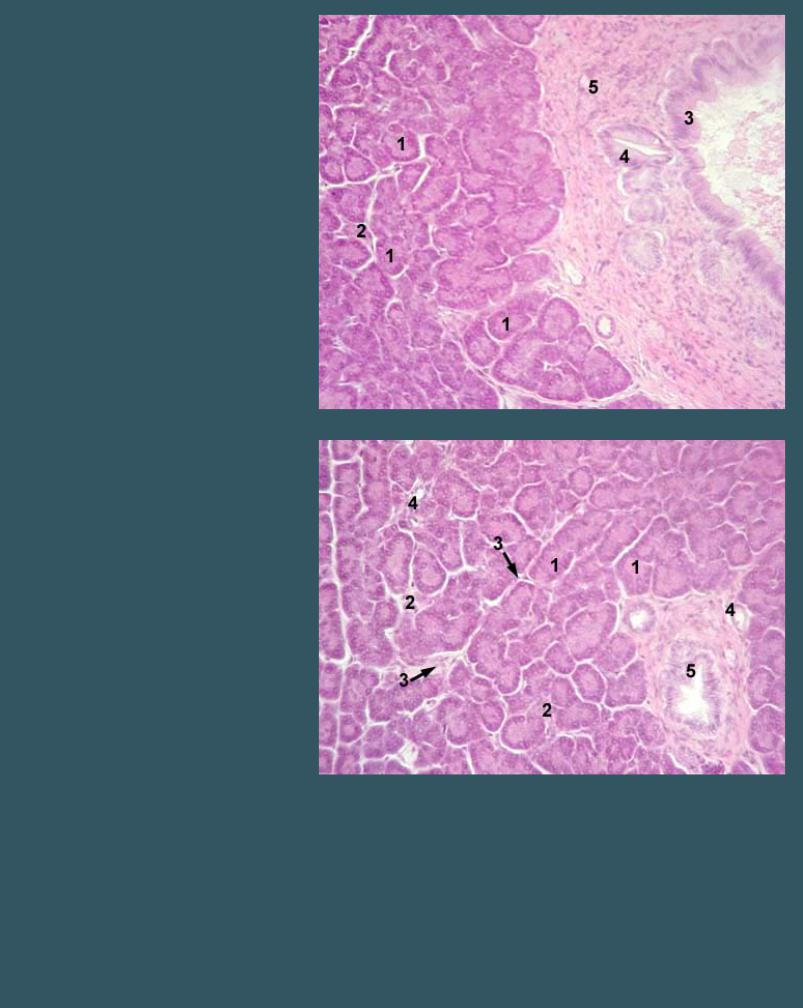

ПОДЖЕЛУДОЧНАЯ ЖЕЛЕЗА

Окраска гематоксилин-эозином

1 - ацинус

2 - островок Лангерганса

3 - общий выводной проток

4 - междольковый выводной проток

5 - междольковая соединительная ткань

ПОДЖЕЛУДОЧНАЯ ЖЕЛЕЗА

Окраска гематоксилин-эозином

1 - ацинус

2 - островок Лангерганса

3 - междольковая соединительная ткань 4 - внутридольковый выводной проток

5 - междольковый выводной проток

ПОДЖЕЛУДОЧНАЯ ЖЕЛЕЗА

Окраска гематоксилин-эозином

1 - ацинус

2 - островок Лангерганса

3 - междольковая соединительная ткань 4 - кровеносные сосуды

ПОДЖЕЛУДОЧНАЯ ЖЕЛЕЗА

Окраска гематоксилин-эозином

1 - ацинус

2 - островок Лангерганса

3 - внутридольковый выводной проток 4 - междольковая соединительная ткань